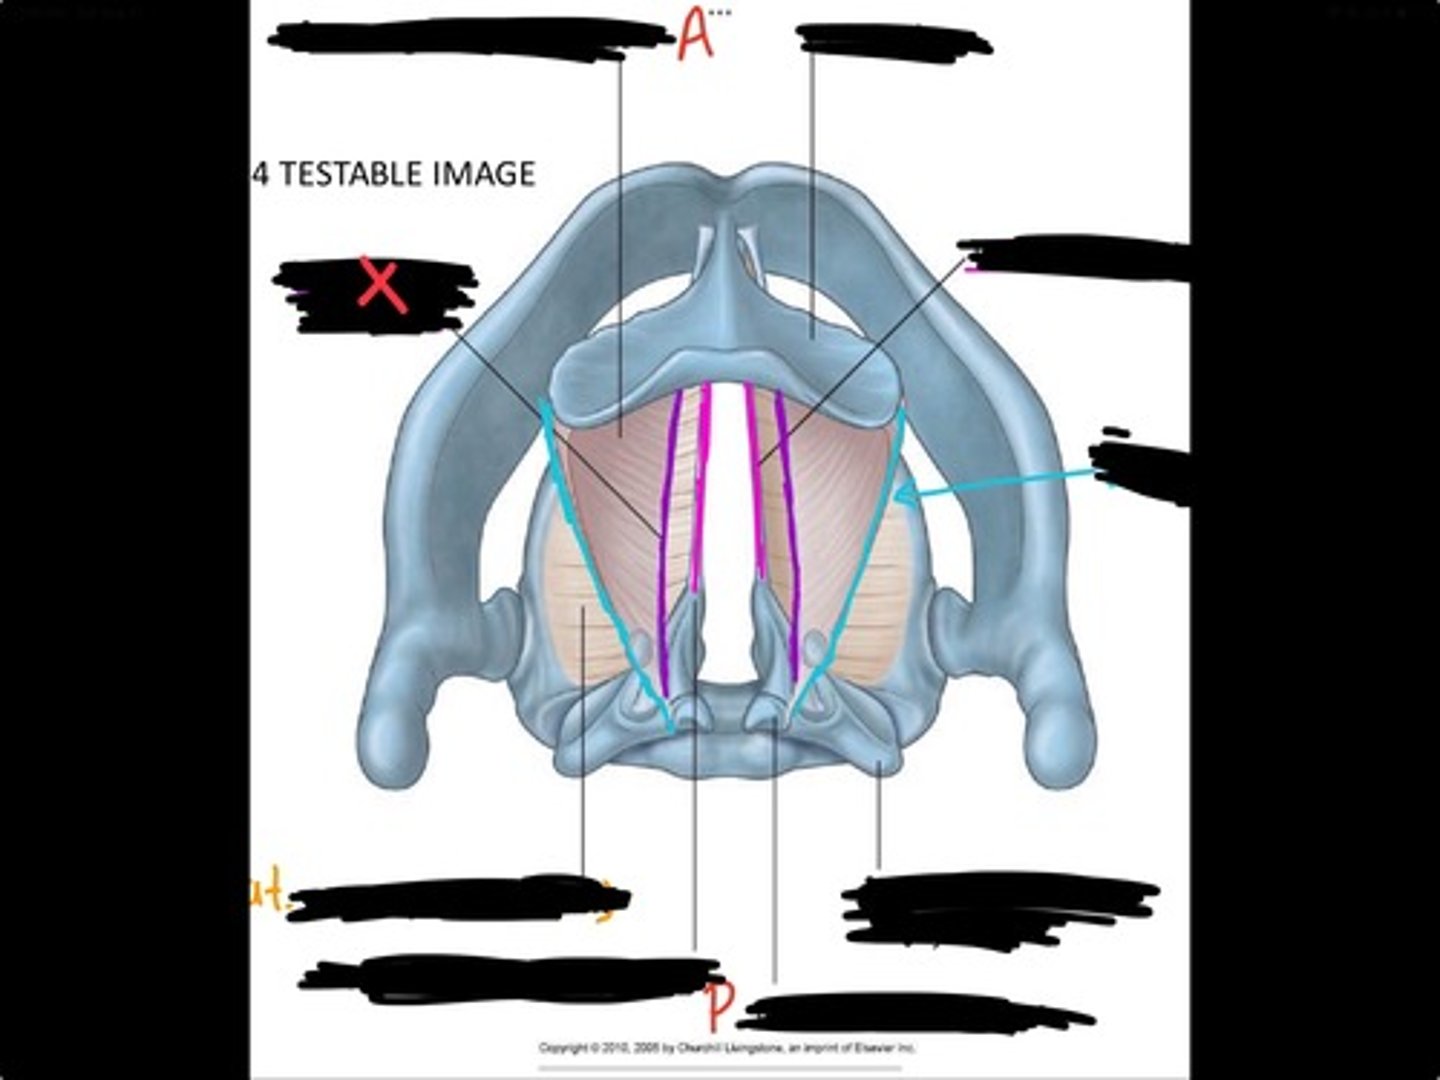

Vocal process of arytenoid

Conus elasticus

Vestibular ligament

Quadrangular membrane

Epiglottis

vocal ligament

Aryepiglottic ligament

Muscular process of arytenoid

Corniculate cartilage

Posterior crico arytenoid

oblique arytenoid

transverse artyenoid

Rima glottidis

Vocal ligament

Vocalis muscle

Lateral cricothyroid ligament

Lateral cricoartenoid